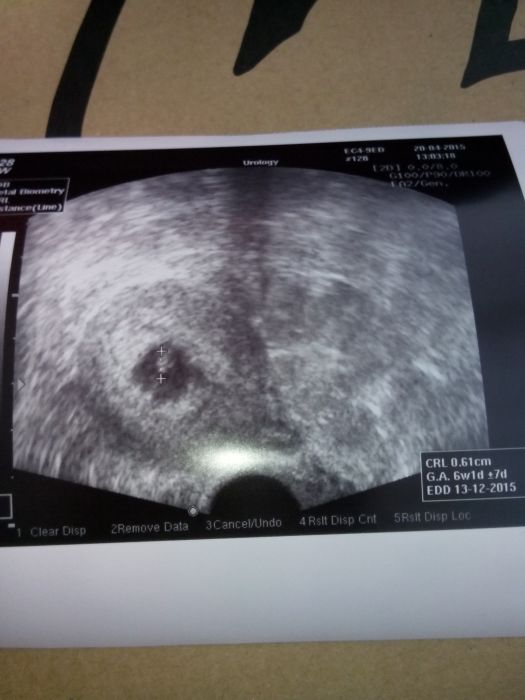

Ahoj holky...tak srdicko dnes bilo....jen mi posunula dr termin...podle pm by to bylo 3.12. Ale podle uz je termin 13.12. ....a mame prvni fotecku do alba.... :-) dalsi kontrola za 3 tydny a to by mi uz dala prukazku....